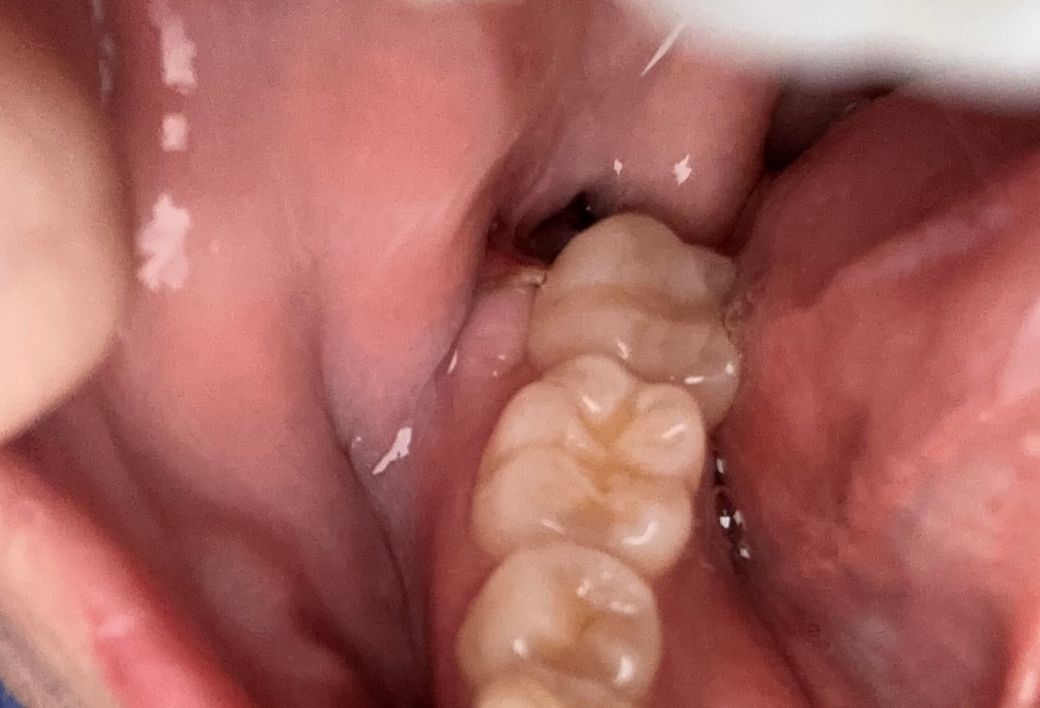

사랑니 발치한지 5일차지만 검정색부분은 뭔가요 ?̊̈

안녕하세요 신경쪽 매복사랑니 발치한지 5일차입니다 실밥은 녹는실이고 치과에서 사용한 실 색은 흰색인걸로 알고 있었는데,,잘 아물고 있나 사진 찍어보니 저 검은색은 뭔가요 ?̊̈.잘 아물고 있는게 맞나요 ?̊̈

구멍인걸까요 ?̊̈

사랑내를 발치하고 나면 발치한 부위에 빈 공간이 생길 수 있습니다. 이 빈 공간은 검은색 또는 검붉은색으로 보일 수 있습니다. 사랑니를 발치한 부위를 열어보거나 자극을 한다면 출혈이 되고 치유가 늦어질 수 있기 때문에 해당 행동을 줄이는 것이 좋습니다.

사진에 보이는건 치아를 빼고나서 빈공간이 어두워서 까맣게 보이는겁니다. 문제가 잇는건 아니니 걱정하지마세요.

사랑니 발치한지 5일차지만 검정색부분은 뭔가요 ?̊̈ ->그냥 발치부위 구멍입니다 1~2달에 걸쳐 잇몸뼈와 잇몸이 차오르게 됩니다